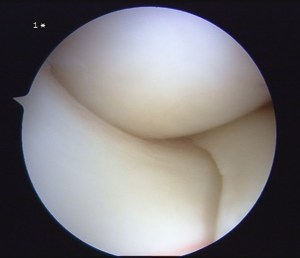

This is a video showing the surgery to remove a torn portion of a lateral meniscus.